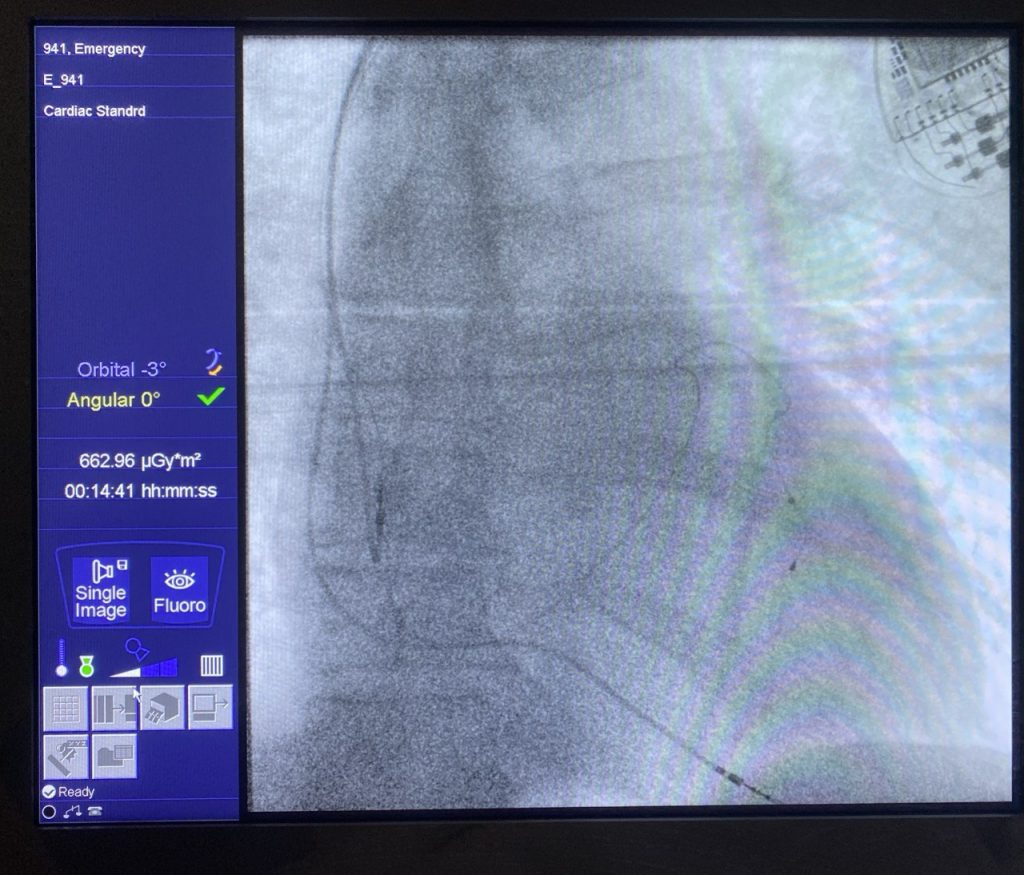

- Імплантація одно- та двокамерних електрокардіостимуляторів (ЕКС).

- Імплантація одно- та двокамерних імплантованих кардіовертерів-дефібриляторів (ІКД).

- Імплантація CRT-P, CRT-D (пристрої кардіоресинхронізуючої терапії).

- Інвазивне електрофізіологічне дослідження серця.

- Радіочастотна катетерна деструкція субстрату аритмії (суправентрикулярні тахікардії, синдром ВПВ, тріпотіння передсердь).